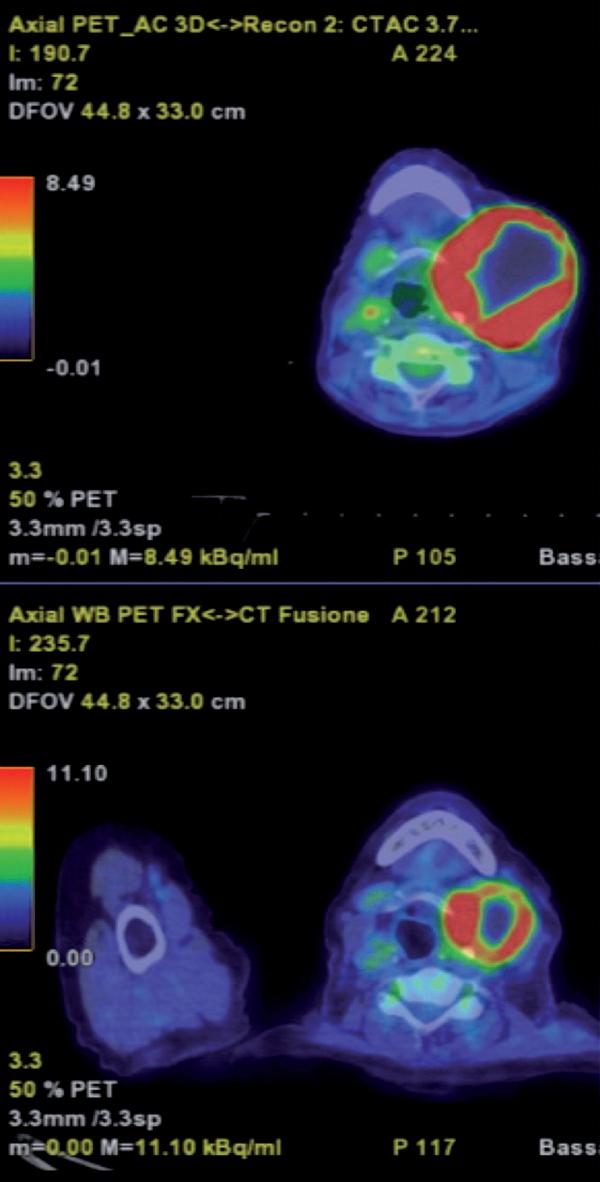

Agosto 2021 PET total body con FDG: “ipercaptazione orofaringea e linfonodale laterocervicale bilaterale” (figure 1 e 2).

Figura 1. PET total body con FDG mostra ipercaptazione orofaringea e linfonodale laterocervicale bilaterale.

Figura 2. PET di esordio che mostra la principale sede di malattia a livello linfonodale laterocervicale sinistro.

„ PET total body: “nella regione orofaringea non sono attualmente documentabili significative focalità ipercaptanti, in regressione metabolica le adenopatie evolutive laterocervicali bilaterali attualmente con modesta ipercaptazione di FDG maggiore a sinistra in esiti attinici”.